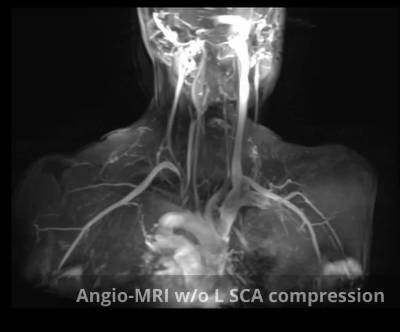

The following tests are required to make an accurate diagnosis:

- Cervical-thoracic CT angiography/Cervical-thoracic MR angiography with compression manoeuvres